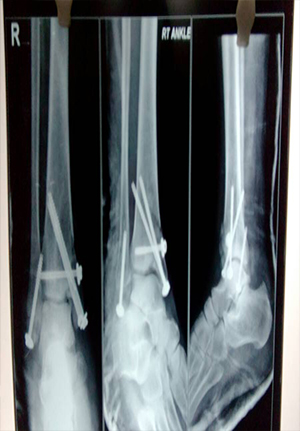

Ankle Fracture fixation

Fracture disocation Ankle treated by ORIF